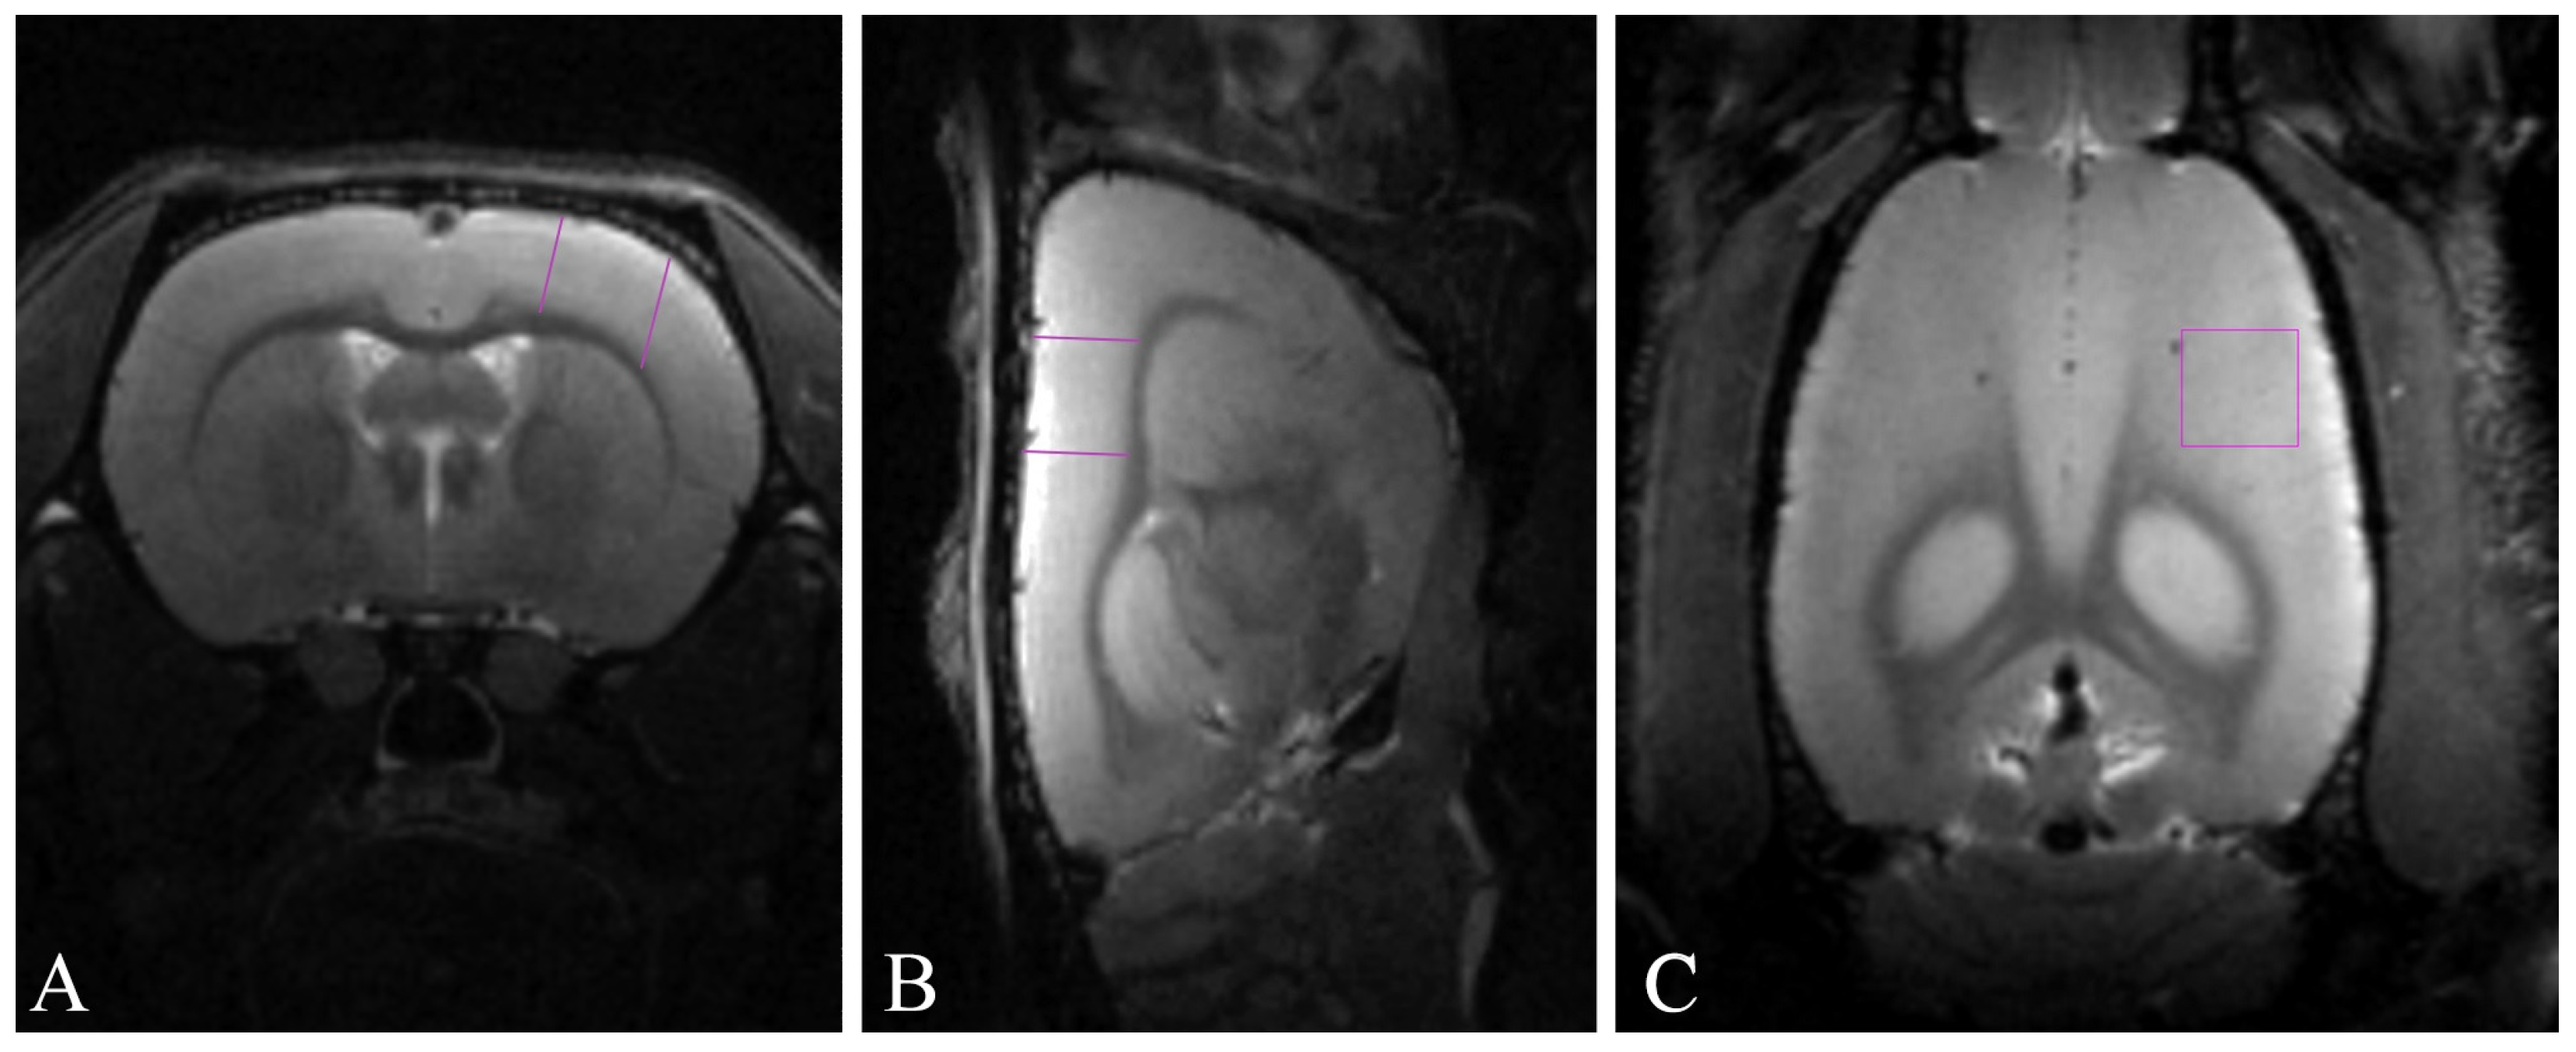

2.2. Sensorimotor Cortex Volume Is Reduced in the Intact, but Not in the Irradiated Rats through Aging

4.5. Magnetic Resonance Imaging-Based Morphometry